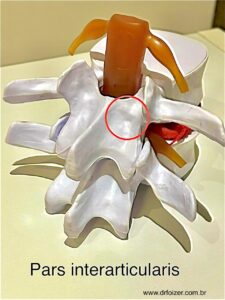

Spondylo é o prefixo grego dessa palavra que significa “vértebra” enquanto seu sufixo “lise” vem da palavra lysis que significa quebra ou falha. A espondilólise (também conhecida como lise dos istmos) é uma fratura de estresse na pars interarticularis (fig.1), uma pequena porção da vértebra.

Fig. 1– O círculo vermelho representa a pars interarticularis no modelo de vértebra típica.

Essa pequena porção da vertebra é um dos responsáveis por manter a união de uma vertebra com a outra através de pequenos “ganchinhos” chamados facetas articulares . O problema é mais comum na região lombar e pode ser consequência de atividades repetitivas que sobrecarregam a coluna, como ginástica, ballet, levantamento de peso e futebol. Ela é frequentemente encontrada em adolescentes e jovens adultos ativos. Geralmente os pacientes possui alguma predisposição para desenvolver esse quadro, ou seja, nem todas as pessoas que praticam essas atividades, irão desenvolver a espondilólise.